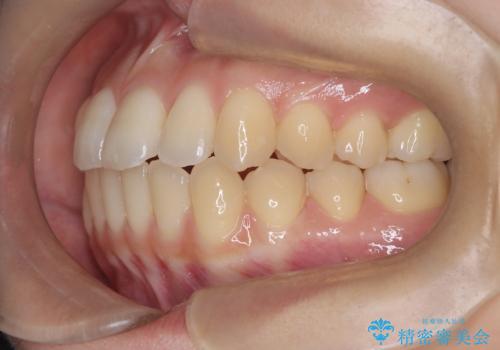

- 前歯のガタガタ(叢生)と、前歯が出ている(突出している)ことを気にされてご来院されました。精密な検査の結果、歯が並ぶスペースと、前歯を引っ込めるスペースの両方が不足していると診断。患者様のご希望に合わせ、透明で目立ちにくいインビザライン(マウスピース矯正)による治療計画を立案しました。スペースの確保は、奥歯全体を奥へ動かす遠心移動と、歯の側面をわずかに削る**IPR(歯間乳頭保護下ストリッピング)**を組み合わせて行い、前歯を効果的に引っ込めることを目指します。

今回の矯正治療では、透明なマウスピース型の装置インビザラインを使用しました。前歯を無理なく引っ込めるスペースを作るため、まず奥歯全体を後方へ移動させる遠心移動を実施。さらに、安全性が確保できる範囲で歯の側面をわずかに削るIPRを併用し、必要なスペースを確保しました。これらの処置により、前歯のデコボコが解消され、前に出ていた前歯も適切に引っ込みました。目立たない装置で治療を完結することで、叢生と突出感が解消され、機能性と審美性が向上した美しい口元を獲得していただけました。